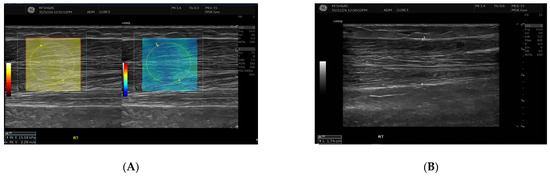

Exploratory Assessment of Muscle Thickness and Stiffness Around Arteriovenous Fistulas Using Shear Wave Elastography

Background/Objectives: Muscle thickness and stiffness near the arteriovenous fistula (AVF) site may influence vascular access function in hemodialysis patients. This exploratory study aimed primarily to describe differences in muscle thickness and stiffness between the AVF-bearing and contralateral limbs, and secondarily to examine [...] Read more.

Background/Objectives: Muscle thickness and stiffness near the arteriovenous fistula (AVF) site may influence vascular access function in hemodialysis patients. This exploratory study aimed primarily to describe differences in muscle thickness and stiffness between the AVF-bearing and contralateral limbs, and secondarily to examine whether these parameters were associated with AVF maturation. This study aimed to compare these muscle parameters between the AVF and contralateral sides and to evaluate their relationship with AVF maturation status. Methods: Thirty participants undergoing hemodialysis were included, comprising 22 with mature AVFs and 8 with non-mature AVFs. Ultrasound examinations measured muscle thickness and stiffness using Shear Wave Elastography (SWE) of the biceps brachii and brachioradialis muscles. Volume flow was recorded in the draining vein and feeding artery. Statistical analyses included paired comparisons, group comparisons, Pearson correlations, and multiple linear regression models. Results: Brachioradialis thickness was significantly reduced on the AVF side compared with the contralateral side (p = 0.013, Cohen’s d = –0.95), particularly in forearm (radiocephalic) fistulas (Wilcoxon p = 0.014, Cohen’s d = –0.95), indicating localized muscle atrophy. No significant side-to-side differences were found for biceps brachii thickness or for stiffness in either muscle (all p > 0.1). Comparisons between mature and non-mature AVF groups showed no significant differences in muscle parameters on the AVF side (all p > 0.4). Conclusions: AVF may lead to asymmetric muscle changes, especially a reduction in brachioradialis thickness, regardless of maturation status, which could affect forearm function. Nevertheless, muscle thickness and stiffness do not appear to predict AVF maturity or vascular access success directly. Full article

Show Figures

Figure 1